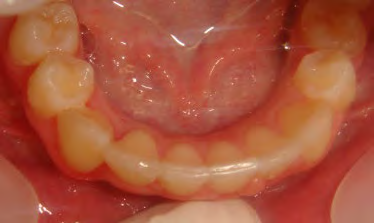

All of the patients below had been told they required extractions by orthodontists, some insisting that they could not be treated without extractions.

They were all treated without extractions, head gear or facemasks at Vakresmil and represent just a small sample of cases treated between 2004–2014.

The patient below had severe crowding of both upper canines and the lower right 5. The upper 4’s and 2’s were actually in contact.

Below are cases treated at Vakresmil without extractions within the last three years. The families had been told, “It is simply not possible for your child to be treated without extractions” by orthodontists. Judge for yourself if that was right or wrong.